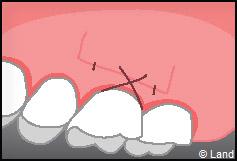

Elles font appel à des lambeaux de gencive restante à proximité des récessions, qui sont déplacés et repositionnés sur la récession.

Dans ce cas le lambeau est déplacé latéralement pour combler la récession.